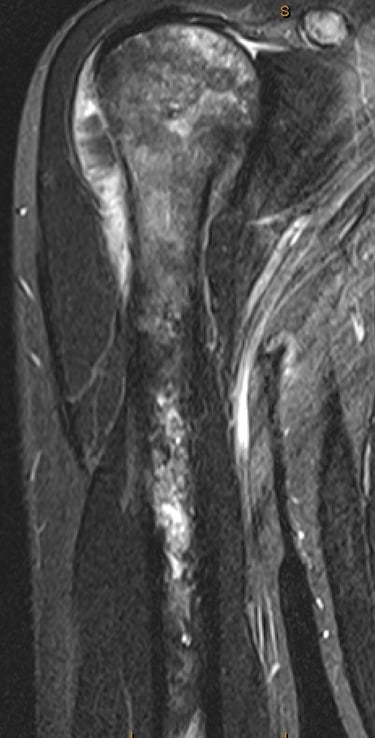

Osteosarcoma is the most common between the ages of 10 to 30 and those > 60 years old. There is no known cause in majority of patients but certain factors are known to increase your risk eg. previous radiotherapy, paget's disease, fibrous dysplasia, bone infarcts or Li Fraumeni syndrome. Most occur around the knee but can occur in any bone. Treatment generally involves combination of chemotherapy and surgery.

Diagnosis of this is generally made with Xrays, CT, MRI, PET scans and a core needle biopsy.